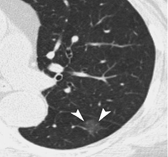

按照CT图像上结节密度的不同,结节分为实性结节和亚实性结节,而亚实性结节又分为部分实性结节和磨玻璃密度结节。实性结节是指看起来和人体软组织密度相似的病灶;磨玻璃密度结节是指肺内模糊的、半透明的结节影;而部分实性结节是指其内既有模糊的部分又有较高密度部分的病灶。在实性结节、部分实性结节和磨玻璃密度结节中,部分实性结节的恶性概率是最高的。

磨玻璃结节 部分实性结节 实性结节